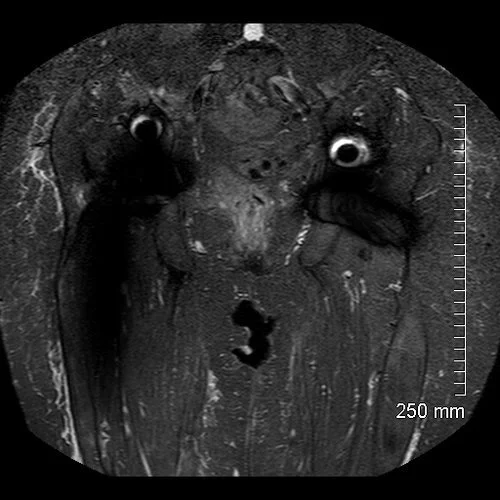

This pre-operative MRI scan reveals soft tissue destruction surrounding the right THR.